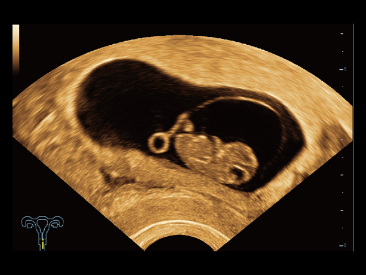

Assim como o n├Łvel de qualidade de imagem premium, o Resona 7 tamb├®m melhora as capacidades de investiga??o cl├Łnica com o revolucion├Īrio Fluxo V para avalia??o hemodin?mica vascular e a aquisi??o de plano mais inteligente do conjunto de dados 3D para diagn├│stico CNS fetal. Combinando a opera??o mais intuitiva baseada em gesto de multi-toques e todos os recursos cl├Łnicos essenciais, Resona 7 est├Ī realmente conduzindo novas ondas na inova??o de ultra-som.